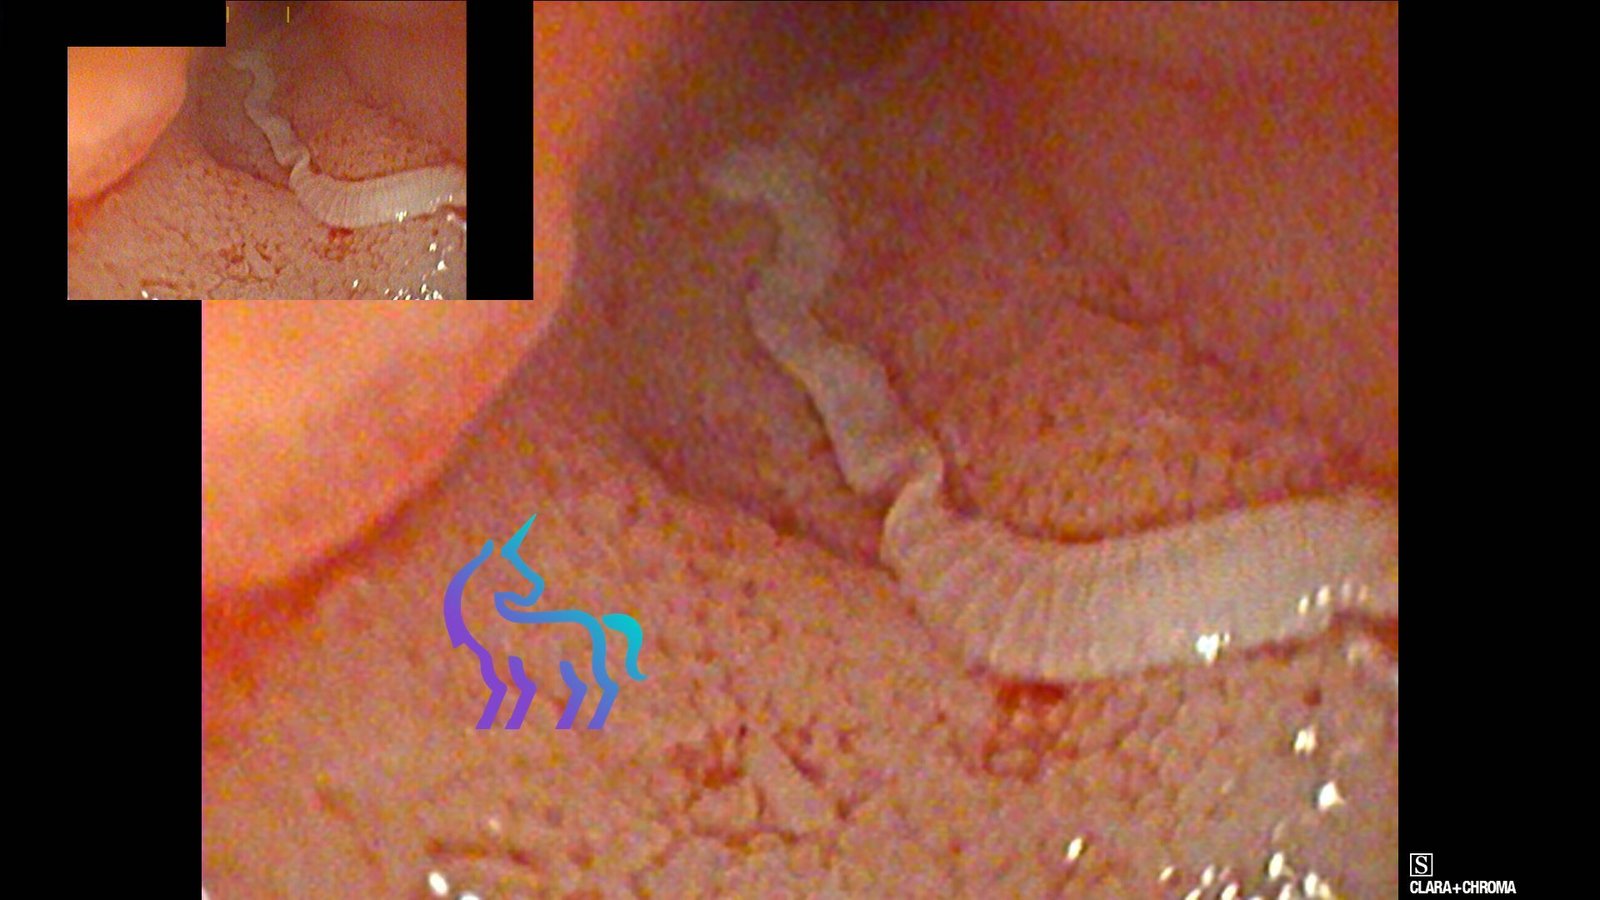

Visualisation directe d’un parasite de type Taenia dans la lumière intestinale lors de la duodénoscopie.

Duodénoscopie : Parasitisme intestinal (Taenia)

Espèce : ChatLors de la duodénoscopie, un parasite de type Taenia a été visualisé dans la lumière intestinale.

Cette découverte explique une partie des troubles digestifs présentés par l’animal et confirme une infestation parasitaire active.

Diagnostic retenu : La visualisation directe permet de confirmer l’infestation. Un traitement antiparasitaire adapté sera mis en place, avec un contrôle clinique et des mesures d’hygiène pour limiter les récidives.